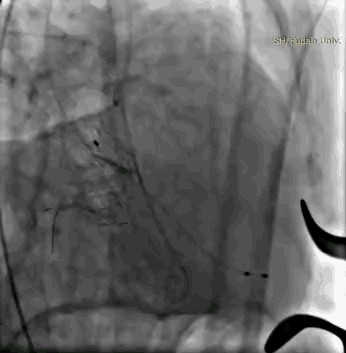

术后左心室造影,二尖瓣反流基本消失